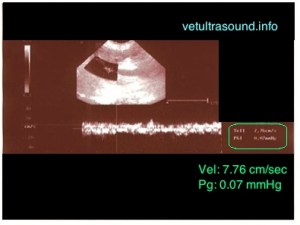

Φυσιολογικά στο σκύλο, η ταχύτητα στην πυλαία φλέβα πρέπει να είναι μεταξύ 10 – 25 cm/sec και η κυματομορφή να είναι με κατεύθυνση προς το ήπαρ με ήπια παλμικότητα η οποία ακολουθεί τον αναπνευστικό ρυθμό. Οποιαδήποτε αλλαγή από το φυσιολογικό μπορεί να σημαίνει πως υπάρχει κάποιο ηπατικό ή καρδιολογικό πρόβλημα. Στην συγκεκριμένη περίπτωση, στην παραπάνω εικόνα, η ταχύτητα είναι μειωμένη και κυματομορφή δεν είναι σταθερή.